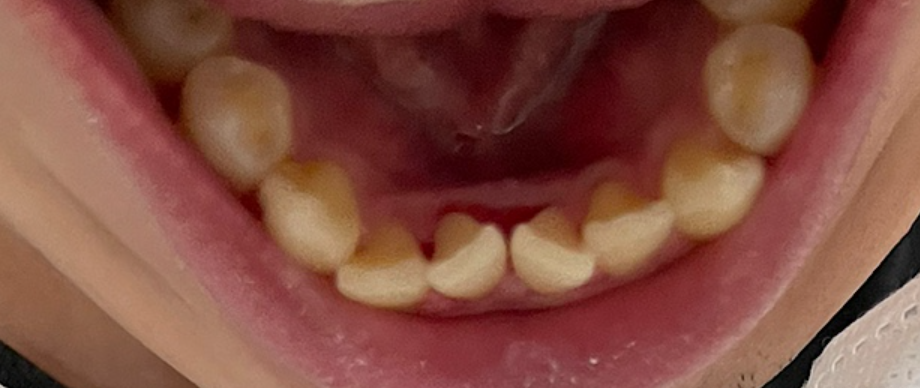

저는 치석이 주로 앞니 안쪽 편에 많이 있었는데요. 제 치석 사진입니다. (혐 주의)

병원에서 편안하게 스케일링을 해 주셔서 치석을 제거할 수 있었습니다.

아쉽게도 치석 떨어지고 나서 사진을 안 찍었었네요. 무슨 금속 덩어린 줄 알았었습니다 ^^;